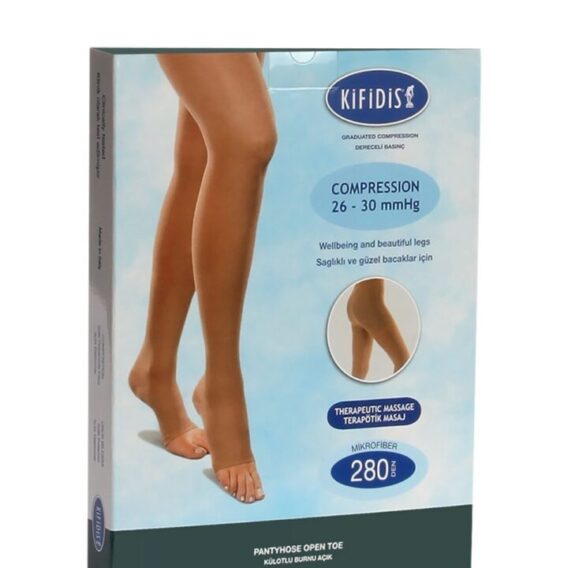

See all productsVaris Çorapları

See all productsEn Çok Satanlar